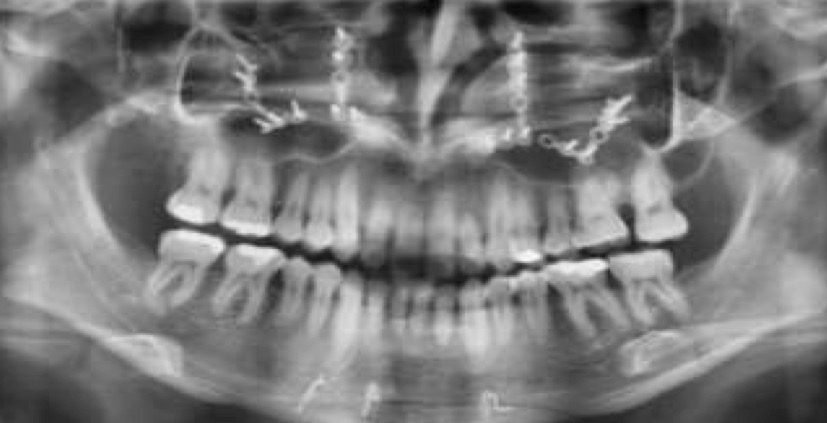

Radiografía panorámica: se observan 28 dientes permanentes presentes, la asimetría mandibular muy marcada con la rama izquierda más ancha que la rama derecha y la desviación de la linea media inferior hacia la derecha a causa de esta asimetría, una de todos las piezas dentales. (Fig. 4)

Fig.4 Radiografía panorámica. Se aprecia como causa del tratamiento previo un acortamiento de las raíces en los incisivos laterales y centrales superiores que no compromete en nuevo tratamiento.